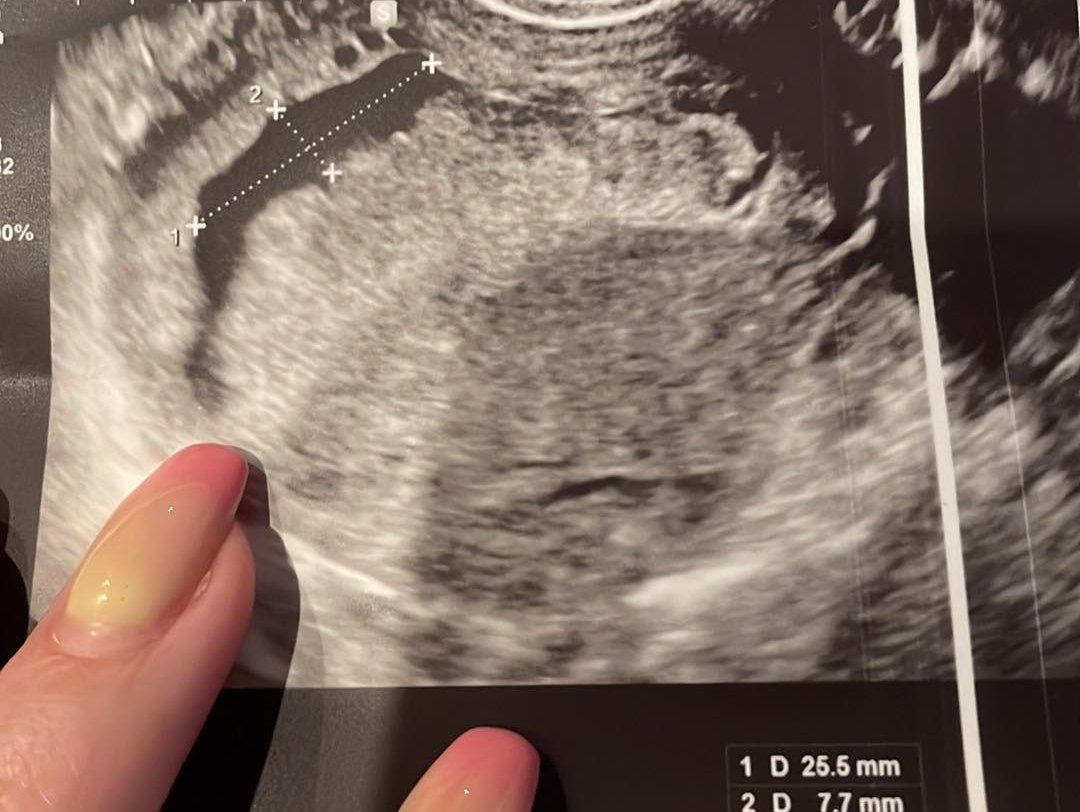

Имам леки притеснения относно кървенето по време на бременност. Някой имал ли е същия проблем и означава ли това спонтанен аборт?

Кървенето по време на бременност може да бъде причинено от различни фактори и не винаги означава спонтанен аборт. Някои жени са имали кървене, но са запазили бременността си. Важно е да се консултирате с вашия лекар и да споделите всички симптоми и притеснения, за да получите професионален медицински съвет.